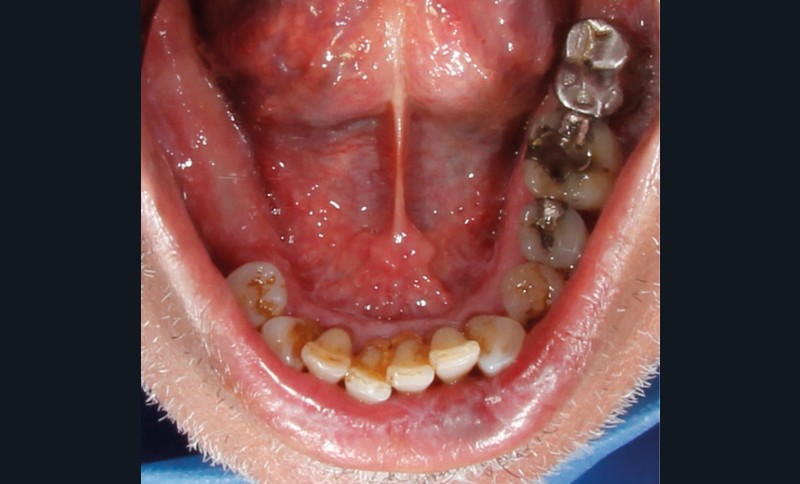

À l’interrogatoire, le patient affirme qu’il a des difficultés à maintenir une hygiène bucco-dentaire satisfaisante du fait des douleurs, et n’a pas pu consulter son chirurgien-dentiste pour son détartrage annuel en raison de la crise sanitaire en cours. L’examen clinique révèle une parodontite chronique (stade 3) généralisée et des lésions jugales (fig. 1 et 2), labiales (fig. 3) et gingivales (fig. 4) érythémateuses et kératosiques. Les lésions kératosiques jugales sont de type réticulé (fig. 1 et 2) ; les lésions kératosiques labiales sont associées à de petites érosions (fig. 3) ; les lésions palatines à des ulcérations (fig. 5). La langue présente une lésion blanche en « tache de bougie » (fig. 6) ; la muqueuse du plancher buccale est saine (fig. 7). Le signe de la pince est négatif. Le patient n’est pas porteur de prothèse dentaire malgré un édentement de moyenne étendue. Aucune lésion cutanée ou génitale n’est rapportée par le patient.

Le diagnostic le plus probable est le lichen plan (LP). On note, au niveau jugal, une kératinisation en réseau marquée par les stries de Wickman. Un phénomène de Koebner (exacerbation…